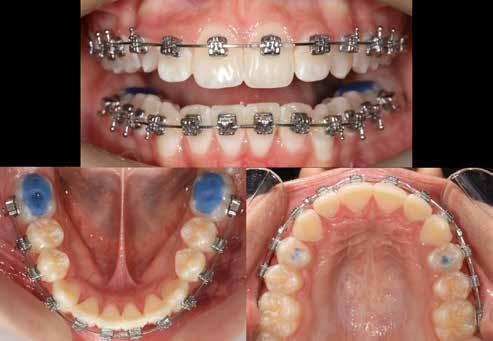

Lány páciensem I. fázisú kezelését 10 évesen kezdtük el bimaxilláris funkciós, kivehető készülékkel. Megfigyelhetőek a class 2-es eltérésnél tipikusan jellemző szűk felső és alsó fo-

gívek, valamint a nagy overjet, a mandibula disztál helyzete, továbbá a felső metszőfogak protrúziója, amelynek kialakulásához sokszor hozzájárul az ujjszopás is (1-3. képek)

A vegyes fogazati kezelési célok a fogívek tágítása és a mandibula meziális irányú növekedésének a biztosítása volt. Fontos, hogy az ilyen típusú készülékeket nem csak éjszaka, hanem napközben is – amennyit csak lehet – hordani kell a minél hatékonyabb működés érdekében. A 18 hónapos első fázisú kezelésnek köszönhetően az alap kezelési célok megvalósultak, sikerült a class 1-es okklúziót beállítani (4-7. képek).

terséges harapásemelés pedig az alsó hatosokra, majd később a felső négyesekre került (8. kép). Az intermaxilláris elasztikus gumihúzás class-2-ess vektorú volt annak érdekében, hogy a disztálharapás korrekciója tökéletes legyen (9. kép). A harapást beállító elasztikus gumihúzásokat – mint minden kezelésnél –, ebben az esetben is folyamatosan, az egész kezelés alatt 24 órában (étkezések kivételével) viselte páciensünk.

A második Pitts-21 fix készülékes fázis ideje 16 hónap volt (10-12. képek)

Az Essix retainerek, az egy fogívre kiterjedő mélyhúzott sínek, valamint a felső és alsó frontfogakra orálisan ragasztott fix retainerek mellett, a harapás sagittális rögzítésében elengedhetetlen szerepe van az ún. Pitts Izom Tréning Splint-nek, amelybe a páciens élharapásban összeharap, így az megakadályozza az alsó fogsor visszamozdulását a disztálharapásos helyzetbe (13. kép)